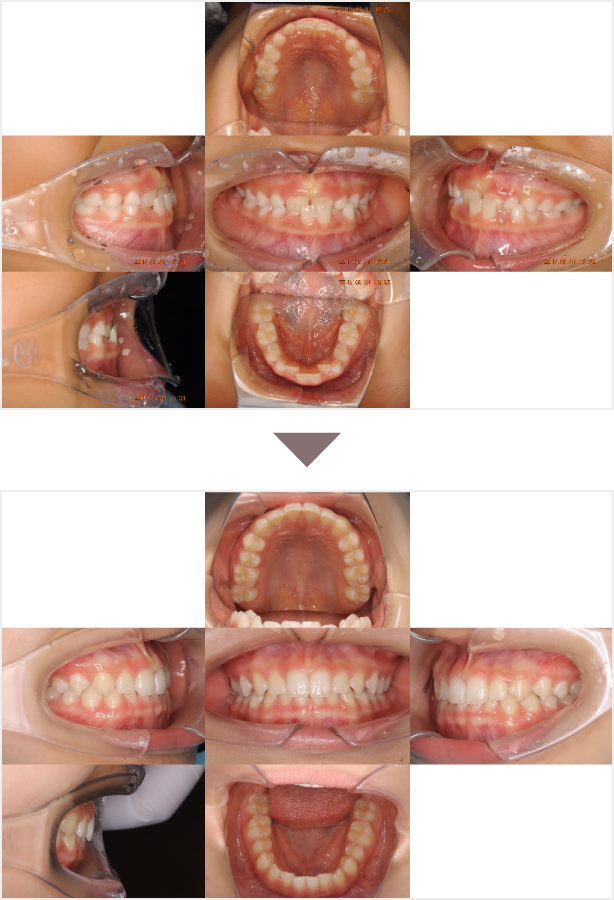

症例叢生

性別

期間6年10ヶ月

治療内容N-Bimler装置、Neo-Capを使用して治療

治療における

副作用・リスク

装着しないと効果は出ません

金額ビムラー装置:550,000円

ネオキャップ:8本

合計:594,000円